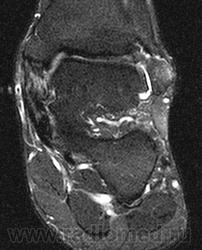

Для определения степени плосковальгусной

деформации, а также состояния сухожильно-

связочного аппарата использовали следующие

диагностические пробы: с подъемом на носки

на одной ноге (рис. 2), симптом «подглядываю-

щих» пальцев. Полученные результаты позво-

ляют судить о состоянии СЗББМ.

Рис. 2. Проба с подъемом на носки на

одной ноге